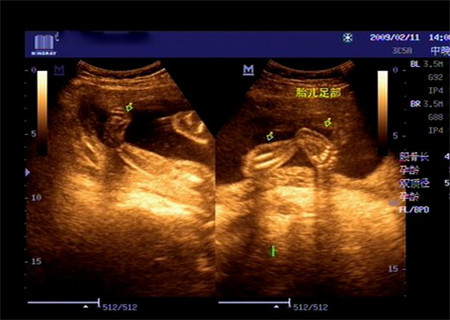

家人听到这样的消息,也非常的心痛,都劝说把胎儿给引产,可是我真的不甘心。在不顾家人的劝阻下我又分别去两个大城市做了四维检查,两家医院的医生都表示孩子是足内翻,因为足内翻会并发其他畸形,这结果也非常的不如意,家人怕承受不了最坏的结果天天都在给我做思想工作。

当宝宝出来的时候看着宝宝这样当妈的心里也不是滋味,为了让宝宝尽快好起来在没出月子后就带孩子去医院看脚,医生表示孩子的左脚中度偏重,右脚轻一点,不过经过治疗—打石膏纠正和手术治疗,还是会正常的,不会影响走路,且其他方面都非常正常。